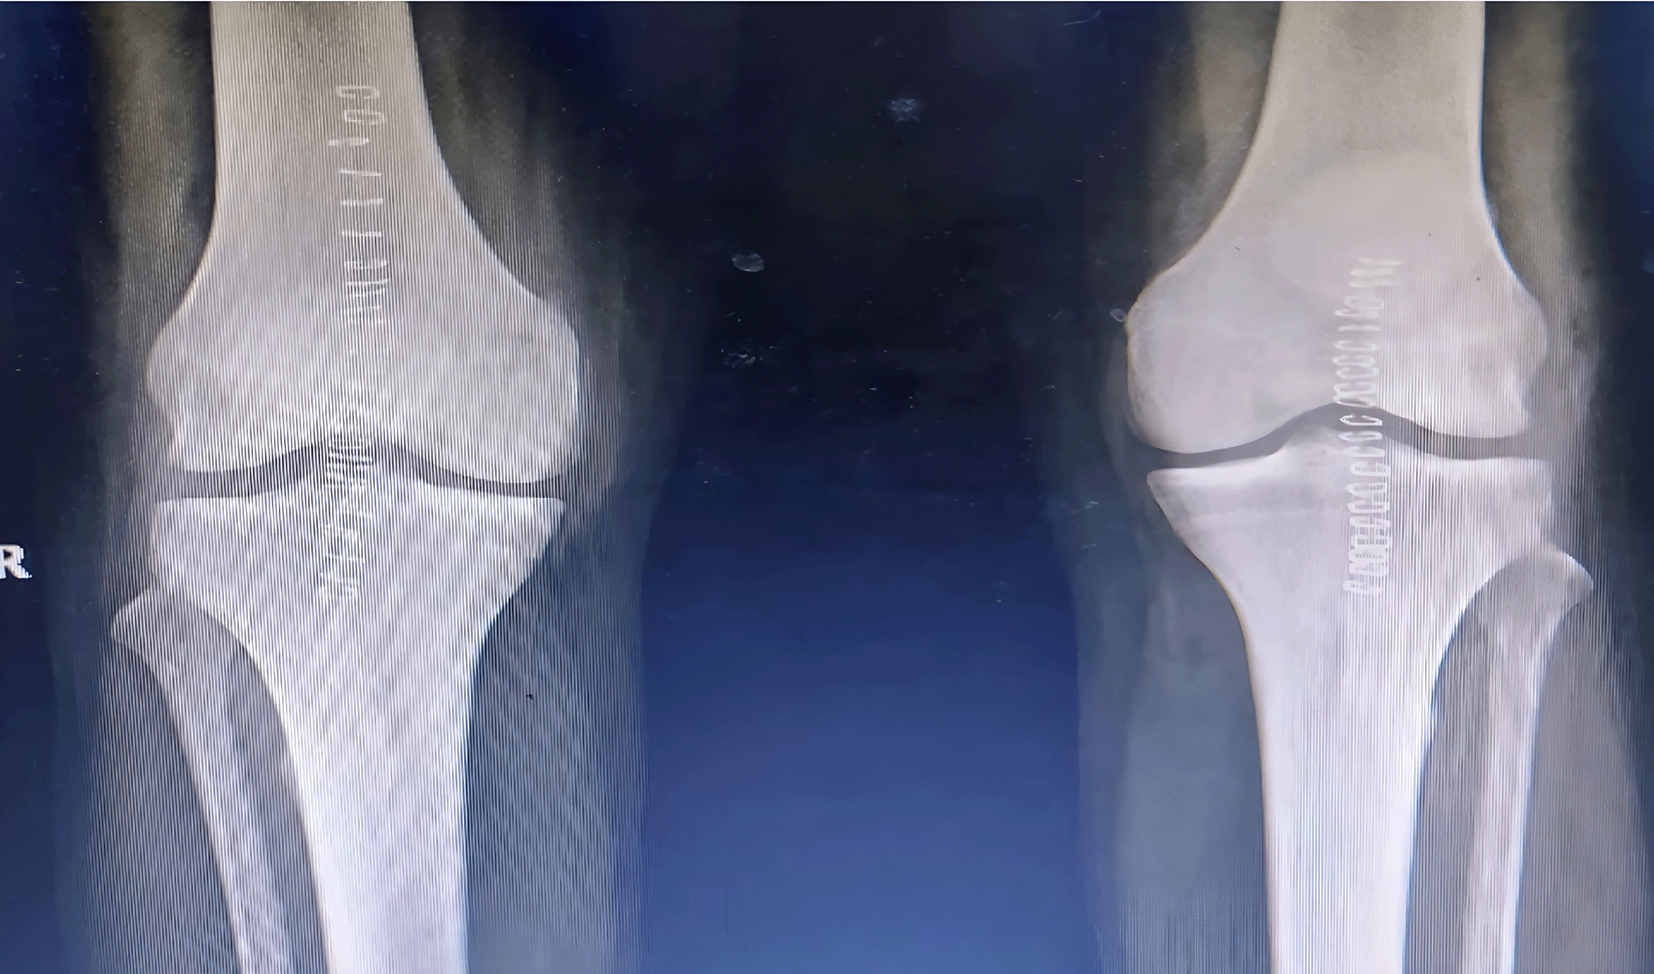

A 61 year old male suffering with ESKD due to nephrosclerosis on hemodialysis for the last 5 years presented to the emergency department with complaints of acute onset pain and swelling in both knees while attempting to stand up from a sitting position. Examination revealed effusion in both knees with a palpable defect in the bilateral patellar tendons and bilateral extension lag. Lateral radiographs showed bilateral patella alta with calcified patellar tendons (Figure 1).

Figure 1. Patella alta noted with calcified patellar tendon.

Surgical repair was performed in a staged fashion with an interval of 2.5 weeks in view of his physiological status. Surgical exploration revealed friable tendon edges with partial avulsion and mid substance tear patterns. The degenerated tissue was excised, and the ends of the tendon were reattached to the patella using suture anchors and non-absorbable sutures, followed by closure of the defects in the medial and lateral paratenon using bioabsorbable sutures (Figure 2).

Figure 2. Post operative radiographs after fixation of tendons with suture anchors.